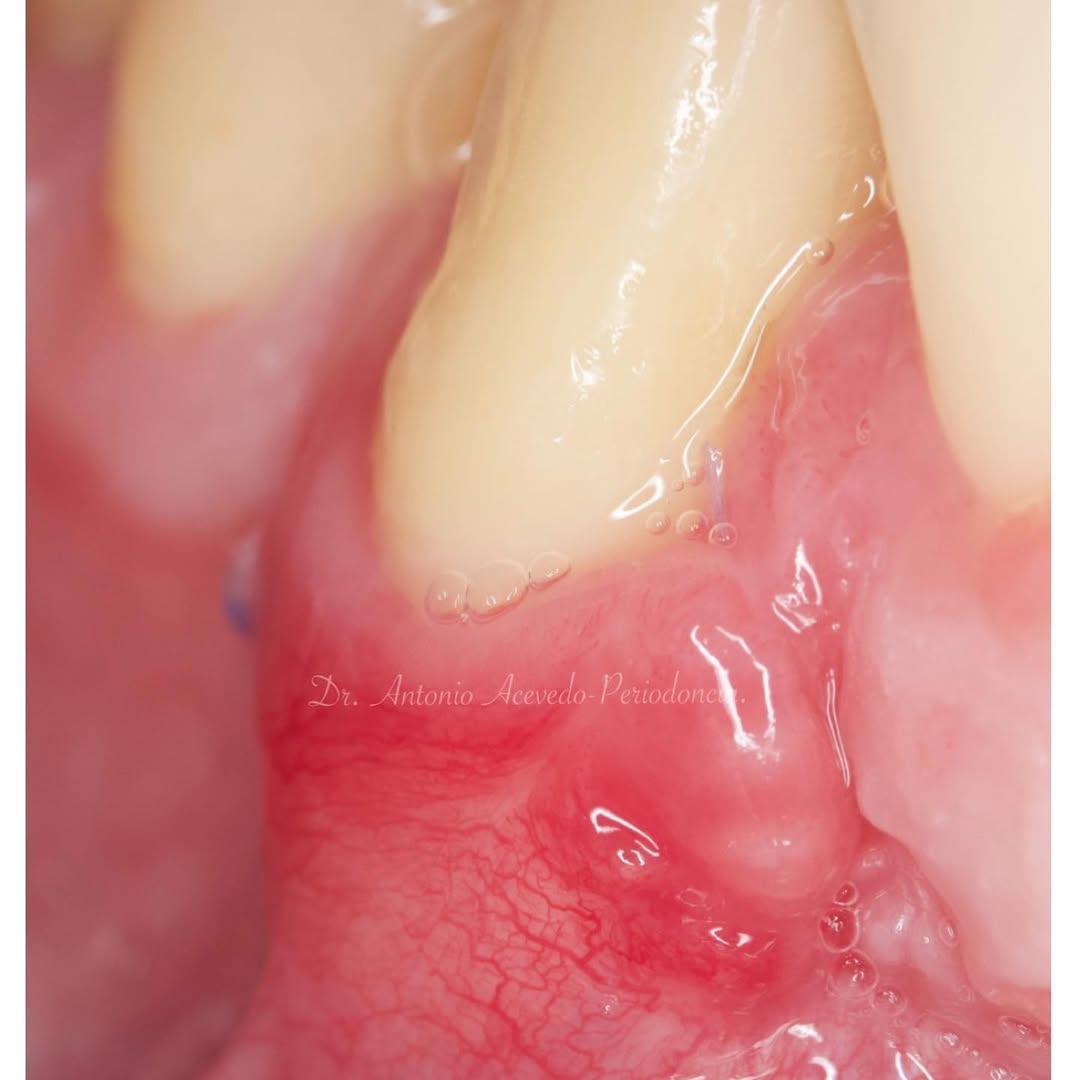

Durante una mañana, asistirás a una Cirugía Mucogingival de recubrimiento radicular de recesiones múltiples en IV y V sextante (36 a 43).

Gracias al uso del microscopio y a la proyección en tiempo real en pantalla, verás exactamente lo mismo que veo yo durante la cirugía, sin tener que estar

Se realizará todo el procedimiento con un microscopio operatorio, lo que permite al alumno ver toda la cirugía en directo en una pantalla en la sala de cirugía.